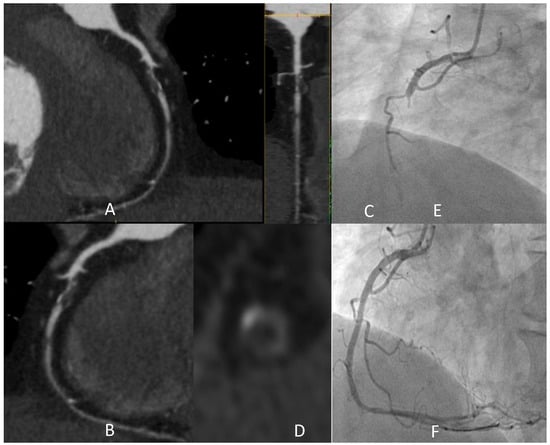

3.3. CCTA in the Planning of CABG